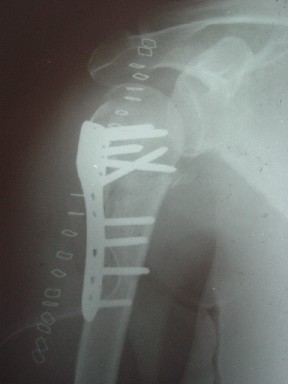

Michael Berenstein 01 Декабрь 2004, 18:22

Висеть будет красиво. У людей физически активного периода жизни нужно открыть, восстановить костную анатомию и восстановить сухожильный аппарат.

В этом плане Locking plate очень хороша так как позволяет начать движения сразу после операции.

Клинические снимки - 3 недели после операции

с уважением М. Беренштейн